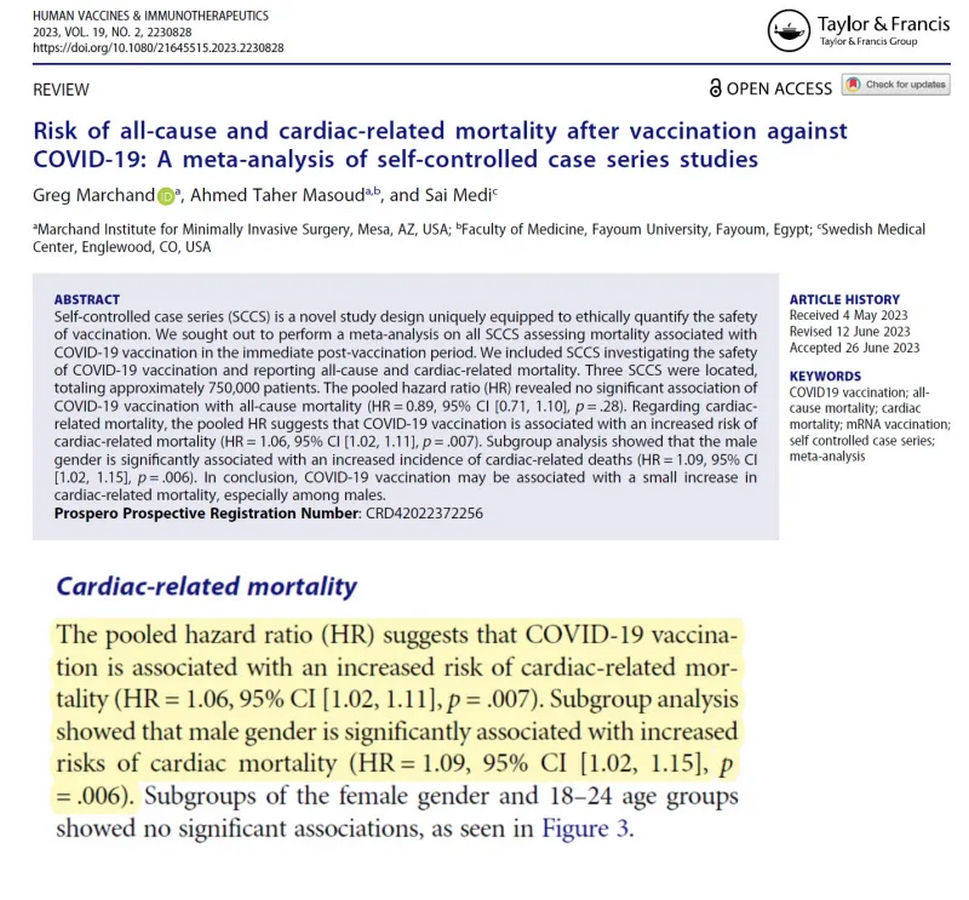

| By Peter A. McCullough, MD, MPH | Von Peter A. McCullough, MD, MPH |

| Because such large populations have been vaccinated with COVID-19, it is difficult to detect secular trends after vaccination. One method is to select a group that has been followed for an extended period of time and then examine what happened in a short period of time after exposure. | Da so grosse Bevölkerungsgruppen mit COVID-19 geimpft wurden, ist es schwierig, säkulare Trends nach der Impfung zu erkennen. Eine Methode besteht darin, eine Gruppe auszuwählen, die über einen längeren Zeitraum beobachtet wurde, und dann zu untersuchen, was in einem kurzen Zeitraum nach der Exposition geschah. |

| Marchand et al. found three self-controlled cohorts in which the first 28 days post-injection after COVID-19 vaccination could be critically examined. Compared with long-term follow-up over 25 months, a pooled hazard ratio (HR) was found for the first 28 days, indicating that COVID-19 vaccination is associated with an increased risk of cardiac mortality (HR = 1.06, 95% CI [1.02, 1.11], p = .007). A subgroup analysis showed that male gender was significantly associated with an increased risk of cardiac mortality (HR = 1.09, 95% CI [1.02, 1.15], p = .006). | Marchand et al. fanden drei selbstkontrollierte Kohorten, bei denen die ersten 28 Tage nach der Injektion nach der COVID-19-Impfung kritisch untersucht werden konnten. Im Vergleich zu einer Langzeitbeobachtung über 25 Monate ergab sich für die ersten 28 Tage eine gepoolte Hazard Ratio (HR), die darauf hinweist, dass die COVID-19-Impfung mit einem erhöhten Risiko für kardiale Mortalität assoziiert ist (HR = 1,06, 95% CI [1,02, 1,11], p = .007). Eine Subgruppenanalyse zeigte, dass das männliche Geschlecht signifikant mit einem erhöhten Risiko für kardiale Mortalität assoziiert war (HR = 1,09, 95% CI [1,02, 1,15], p = .006). |

| Marchand G, Masoud AT, Medi S. Risk of all-cause mortality and cardiac mortality after vaccination with COVID-19: a meta-analysis of self-controlled case series studies. Hum Vaccin Immunother. 2023 Aug 1;19(2):2230828. doi: 10.1080/21645515.2023.2230828. PMID: 37534766; PMCID: PMC10402862. | Marchand G, Masoud AT, Medi S. Risiko der Gesamtmortalität und der kardialen Mortalität nach Impfung mit COVID-19: Eine Metaanalyse von selbstkontrollierten Fallserienstudien. Hum Vaccin Immunother. 2023 Aug 1;19(2):2230828. doi: 10.1080/21645515.2023.2230828. PMID: 37534766; PMCID: PMC10402862. |

| As Hulscher et al. show, the most important mechanisms for cardiac death are myocarditis in younger human beings and the progression of atherosclerotic cardiovascular disease in older human beings. Importantly, COVID-19 vaccines can also trigger cardiac arrest in patients with coronary artery disease or non-ischaemic cardiomyopathy in the absence of myocarditis. Finally, COVID-19 vaccines increase the risk of blood clotting, and on this basis, fatal strokes and venous thromboembolism also contribute to cardiovascular death. | Wie Hulscher et al. zeigen, sind die wichtigsten Mechanismen für den Herztod die Myokarditis bei jüngeren Menschen und das Fortschreiten der atherosklerotischen Herz-Kreislauf-Erkrankung bei älteren Menschen. Wichtig ist, dass COVID-19-Impfstoffe bei Patienten mit koronarer Herzkrankheit oder nicht-ischämischer Kardiomyopathie auch ohne Myokarditis einen Herzstillstand auslösen können. Schliesslich erhöhen COVID-19-Impfstoffe das Risiko der Blutgerinnung, und auf dieser Grundlage tragen auch tödliche Schlaganfälle und venöse Thromboembolien zum kardiovaskulären Tod bei. |

| These data show that the 28-day post-injection period is the longest in vaccinated persons. It is important not to compare these data with those of unvaccinated people, who have a much lower risk because they have not been exposed to the mRNA or adenoviral DNA that codes for the deadly Wuhan spike protein. | Diese Daten zeigen, dass der Zeitraum von 28 Tagen nach der Injektion bei den geimpften Personen am längsten ist. Es ist wichtig, diese Daten nicht mit denen von Ungeimpften zu vergleichen, die ein viel geringeres Risiko haben, da sie nicht mit der mRNA oder der adenoviralen DNA in Kontakt gekommen sind, die für das tödliche Wuhan-Spike-Protein kodiert. |

| SOURCE: CARDIAC MORTALITY UP DURING 28 DAYS AFTER COVID-19 VACCINATION IN SELF-CONTROLLED STUDIES FROM ENGLAND, ITALY, UNITED STATES | QUELLE: CARDIAC MORTALITY UP DURING 28 DAYS AFTER COVID-19 VACCINATION IN SELF-CONTROLLED STUDIES FROM ENGLAND, ITALY, UNITED STATES |

| Source: https://uncutnews.ch/mccullough-herz-todesfaelle-steigen-einen-monat-nach-der-impfung-sprunghaft-an/ | Quelle: https://uncutnews.ch/mccullough-herz-todesfaelle-steigen-einen-monat-nach-der-impfung-sprunghaft-an/ |